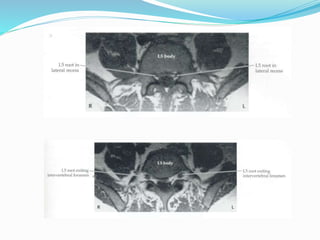

RAIZES NERVOSAS X VERTÉBRAS, DISCOS E

LIGAMENTOS